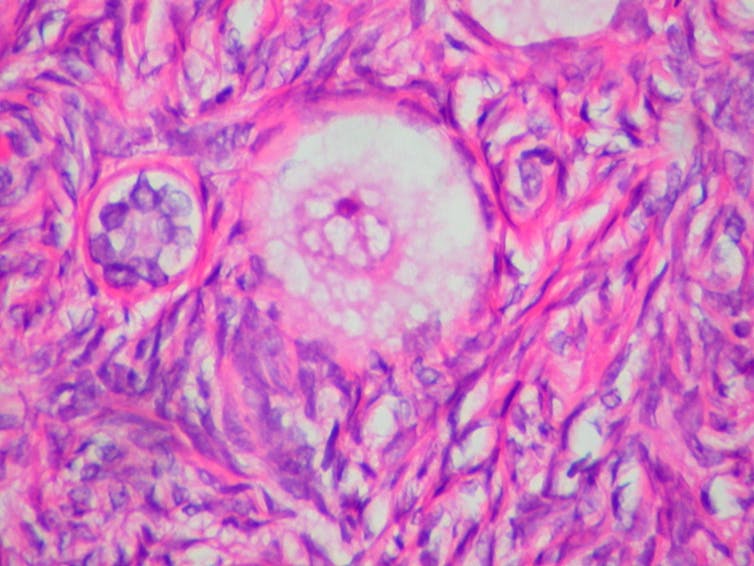

Ed Uthman / Wikimedia Commons., CC BY